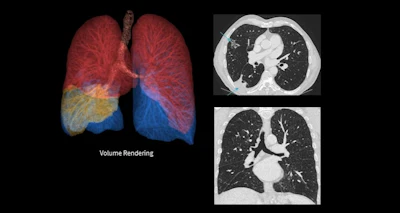

True Definition DL is designed for high-resolution imaging in pulmonary, musculoskeletal, and inner ear applications. It enhances spatial resolution across multiple directions, integrates artifact suppression, and supports a high-definition mode to improve visibility of fine anatomical structures such as small airways, pulmonary nodules, and trabecular bone patterns.

The tool also offers a 1024 matrix for high-resolution display and enables chest imaging in under one second, the company said.